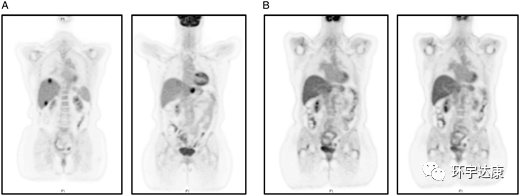

文献中报道了一位61岁的女性被诊断为胰腺导管腺癌,胰腺体内有一个2.5cm的肿块,肝脏有1.2cm的转移病灶,基因检测发现NTRK1基因融合阳性,在接受拉罗替尼治疗后,胰腺和肝脏的病灶都明显缩小。

CT扫描:(A)治疗前(B)拉罗替尼治疗后

PET-CT扫描:(A)治疗前(B)拉罗替尼治疗后